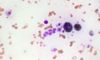

Describe the appearance of mast cells.

Large cells containing a lot of granules

Describe the appearance of macrophages.

Large cells with lots of cytoplasm

Describe the appearance of macrophages in granulomas.

Epithelioid macrophages - they have a lot of cytoplasm making them look like epithelial cells

What do macrophages in granulomas fuse together to form?

Langerhans giant cells